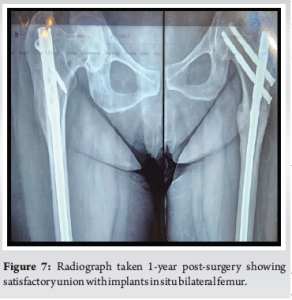

Six weeks into rehabilitation, during one of the mobilization sessions, the patient reported pain at the site of prophylactic nailing in the right femur. Radiographs revealed a minimally displaced fracture in the proximal third of the right femur (Fig. 6). Conservative management was pursued due to the absence of significant displacement or angulation, which was probably due to the prophylactic nail in situ. Mobilization was restricted to bedside exercises for 6 weeks, followed by a gradual return to full weight-bearing activity. There was no complaint of worsening of pain or any other symptoms with this conservative approach. With regular clinical and radiological follow-ups, the patient demonstrated progressive healing, transitioning to single crutch-assisted ambulation by 6 months. One-year post-surgery, complete bilateral fracture consolidation was observed (Fig. 7), and the patient achieved unaided, pain-free mobility. She is still under follow-up and is doing well, with no further symptoms so far.